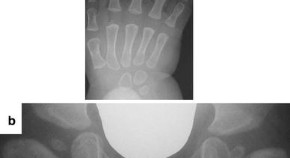

Andrea Superti-Furga, Ron Wevers, Clara van Karnebeek, Luisa Bonafé and colleagues identify mutations in NANS, which encodes the sialic acid synthase, in nine individuals with severe infantile-onset developmental delay and skeletal dysplasia. They describe abnormal metabolites accumulating because of deficient NANS enzyme activity and show that impaired sialic acid synthesis in zebrafish perturbs skeletal development, which can partially be rescued by supplementation with exogenous sialic acid.